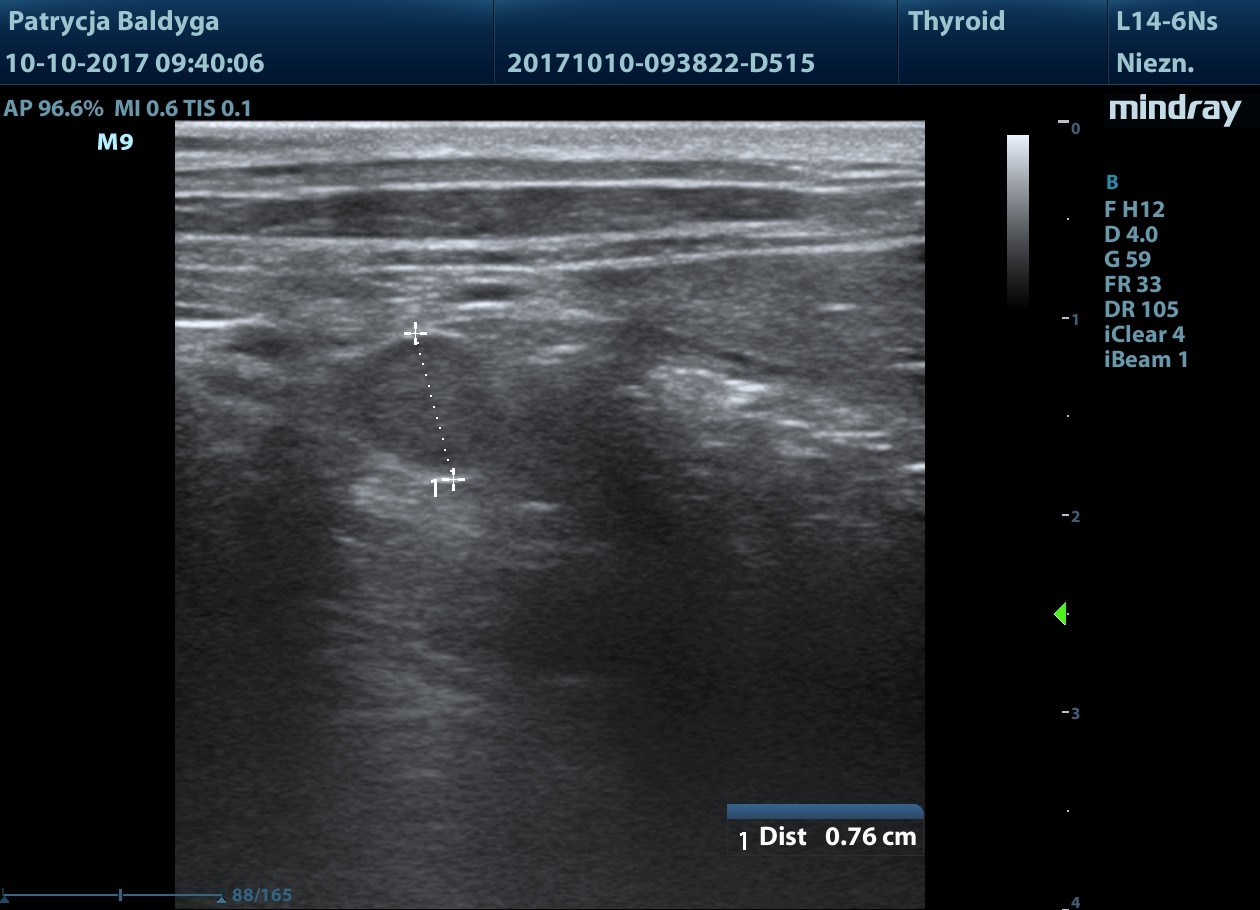

Jelito grube w przewadze w st. zapalnym, ściana o zachowanej wartwowości, pogrubiała zap. do 2,5 mm

naciekowa, śródścienna, hipoechogenna, niesymetryczna 6-18 mm, dł. 2,5 cm, warstwowość w tym miejscu zatarta, obecny okoliczny, nieznaczny odczyn zapalny (pod koniec filmu 3), ww, chłonne okrężnicze środkowe reaktywne, powiększone, hipoechogenne, zokrąglone, śr. ok. 7-8 mm